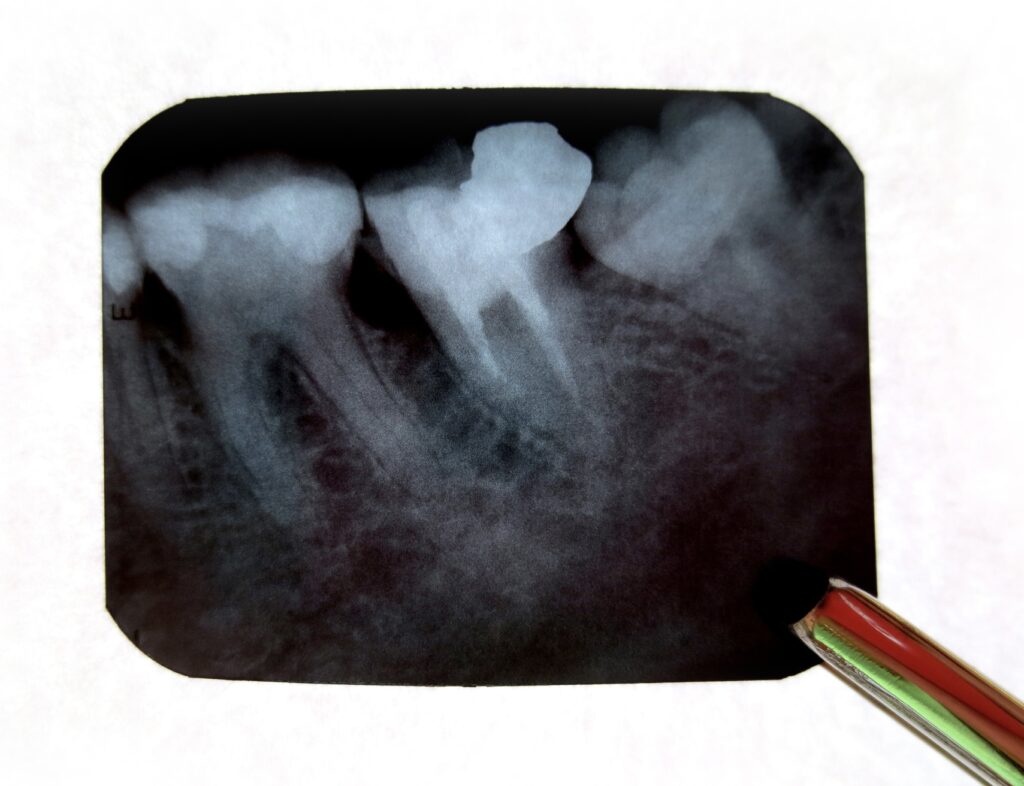

③ デンタルレントゲン

特定の歯を詳しく確認するための小さなレントゲンです。

虫歯や歯根の状態、歯周病の進行などを詳細に確認する際に使用されます。